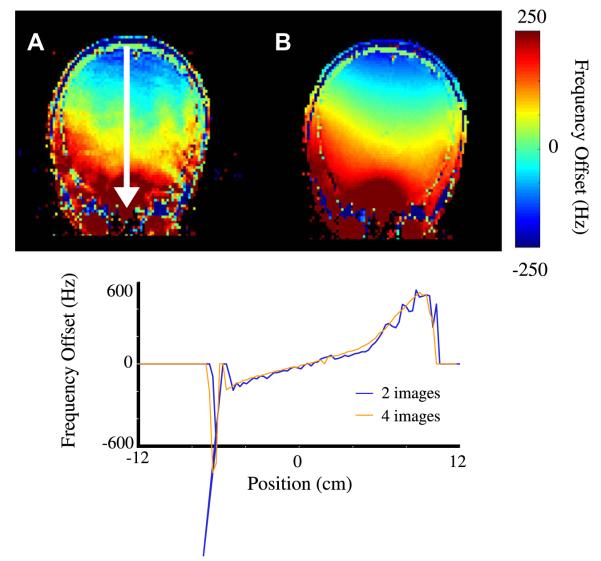

The improved precision of a standard gradient-echo field-map using two and four images is demonstrated in Fig. 3. The improvement in precision with the increased number of images is clear. A typical mapping protocol will allow time for between 3 and 6 images. These results show that significant improvements in precision can be made with each additional image in the acquisition. Therefore, care should be taken to collect as many images as possible while staying within acceptable acquisition times.

Fig. 3.

Axial field maps using (A) 1 delay whereby two images of τj = 0 and 0.33 ms are collected, and (B) using temporal unwrapping of 3 delays (4 images) with τi = 0, 0.33, 1.0 and 3.0 ms, and field traces as indicated by white arrows.